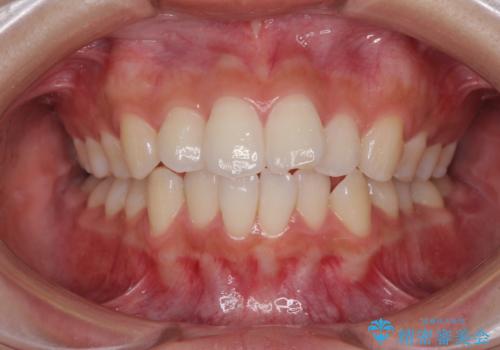

話しにくい歯並びの改善 抜歯矯正治療と前歯の審美治療

前歯の後戻りを部分矯正で整った歯並びへ

前歯のデコボコを治したい 費用を抑えた抜歯矯正

前歯をきれいに整えたい ワイヤー装置での非抜歯矯正